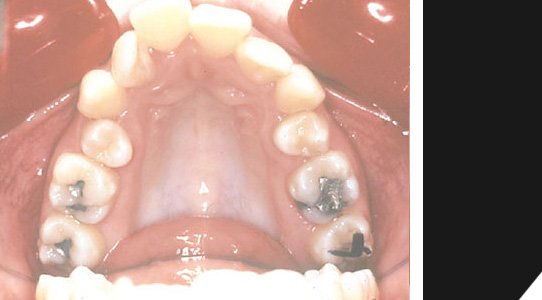

Schneidezähne oben stehen zu eng, untere Front besteht nur aus drei Zähnen.

Eine deutliche Fehlstellung des Frontbereichs...

Im unteren Bereich sind nur drei Frontzähne vorhanden...